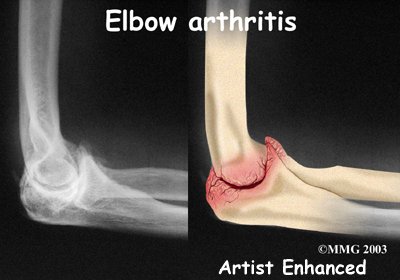

In order to help determine if OA is present you will probably need to get standard X-rays. X-rays are usually the best way to see what is happening with your bones if OA is suspected. X-rays can help your health care professional assess the damage and track how your joint changes over time. X-rays can also help your health care professional see how many bone spurs are present and if there are any loose bodies in the joint. X-rays also show the size of the joint space and how much articular cartilage is left.

In order to help determine if OA is present you will probably need to get standard X-rays. X-rays are usually the best way to see what is happening with your bones if OA is suspected. X-rays can help your health care professional assess the damage and track how your joint changes over time. X-rays can also help your health care professional see how many bone spurs are present and if there are any loose bodies in the joint. X-rays also show the size of the joint space and how much articular cartilage is left.